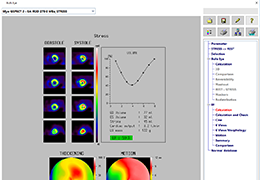

Performs 3D reconstruction and volume rendering.

Multi-planar slicing.

Side-by-side comparative assessment for pre- and post-operative scans.